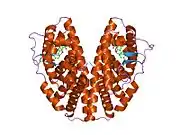

ERβ is a member of the family of estrogen receptors and the superfamily of nuclear receptor transcription factors. The gene product contains an N-terminal DNA binding domain and C-terminal ligand binding domain and is localized to the nucleus, cytoplasm, and mitochondria. Upon binding to 17-β-estradiol, estriol or related ligands, the encoded protein forms homo-dimers or hetero-dimers with estrogen receptor α that interact with specific DNA sequences to activate transcription. Some isoforms dominantly inhibit the activity of other estrogen receptor family members. Several alternatively spliced transcript variants of this gene have been described, but the full-length nature of some of these variants has not been fully characterized.[7]